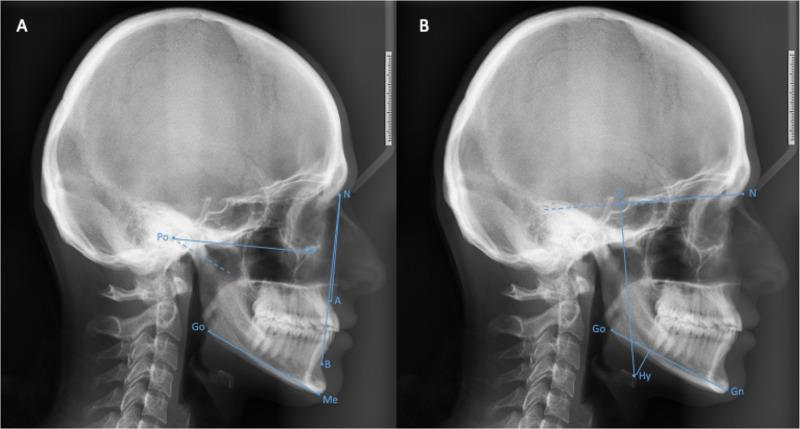

Following the acquisition of their written informed consent, 330 patients who applied for orthodontic treatment and who met the inclusion requirements were invited to take part in the study by completing the following questionnaires: Beck Depression Inventory (BDI), Pittsburgh Sleep Quality Index (PSQI), and Oral Health Impact Profile (OHIP-14). According to criteria like incomplete questionnaires, BDI score above 17 and body mass index higher than 30, 50 patients' data were excluded. Two hundred and eighty participants were classified according to their sagittal and vertical patterns and the hyoid bone distance to the mandibular plane (GoGn) and anterior cranial base (SN). Oral health-related quality of life and its components, sleep quality and its components were compared between groups.

The PSQI scores for the sagittal and vertical groups did not significantly differ from each other, except for the normodivergent and hyperdivergent groups' total scores. It was observed that when the Hyoid-SN line distance decreased; the sleep quality decreased with an increase in the "sleep disturbance" and "daytime dysfunction". Neither the Hyoid-GoGn distance nor vertical or sagittal patterns were found to be related to OHRQoL. There was a significant correlation between OHIP-14 and PSQI.